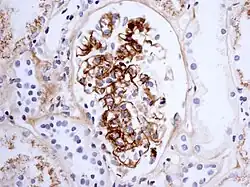

La maladie se caractérise par un dépôt d'immunoglobuline de type A1 dans les parois des vaisseaux et dans le tissu rénal (mésangium).

- enfin, une atteinte rénale glomérulaire d'intensité variable dans environ 40 % des cas, caractérisée en général par une protéinurie, une hématurie, en général sans insuffisance rénale aiguë ;